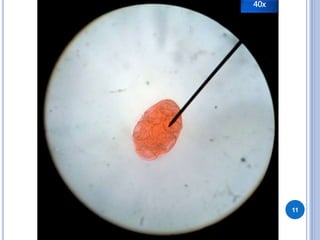

Este documento describe las características generales y las etapas del ciclo de vida de Dipylidium caninum. Explica que la larva cisticercoide es la etapa infectante, mientras que las proglótides en las heces son la etapa diagnóstica. Se transmite por la ingestión de pulgas infectadas y se diagnostica mediante una prueba de lugol en las heces. El huésped definitivo es el perro y los huéspedes accidentales son las ratas y los humanos.